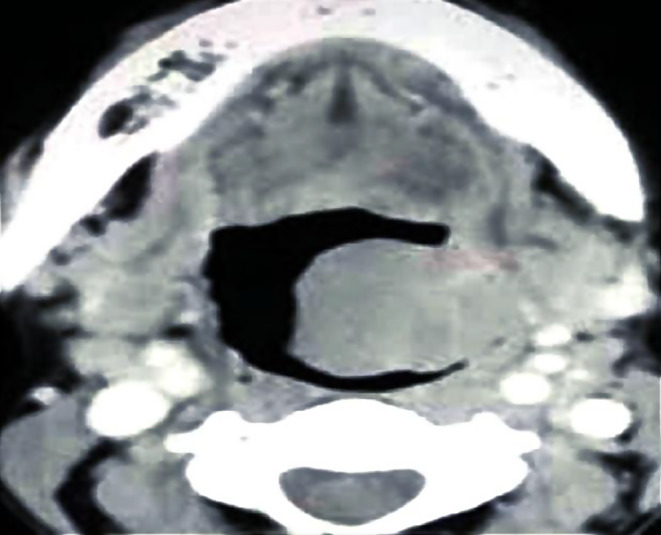

A Computed Tomography (CT) scan identified a fat attenuation cyst in the left tonsillar bed, with no evidence of intracranial extension. It also showed a Homogeneous soft tissue density mass measuring 2.3 cm X 3 cm on left side of oropharynx arising from tonsillar floor, crossing the midline and causing effacing the oropharyngeal column partially. It is well away from ipsilateral carotico-jugular complex that is appears patent. No surrounding enlarged cervical lymph nodes. The CT-scan demonstration is given in Fig. 2.

Fig. 2.

Showing the CT scan findings of the patient